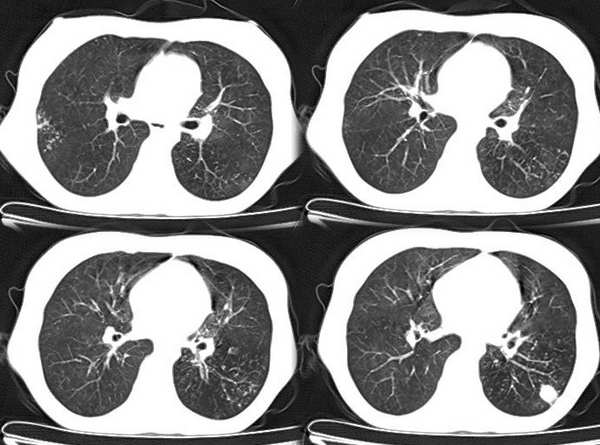

以下是引用x线在2006-2-2 17:37:00的发言:[br]结合病史支持“ct拟诊:双侧tb,左下叶结核球,左下叶局限性轻度支扩。”双下叶及左舌叶淡薄的毛玻璃密度影,我考虑为炎性渗出。另:是否合并霉菌感染须进一步检查确定。